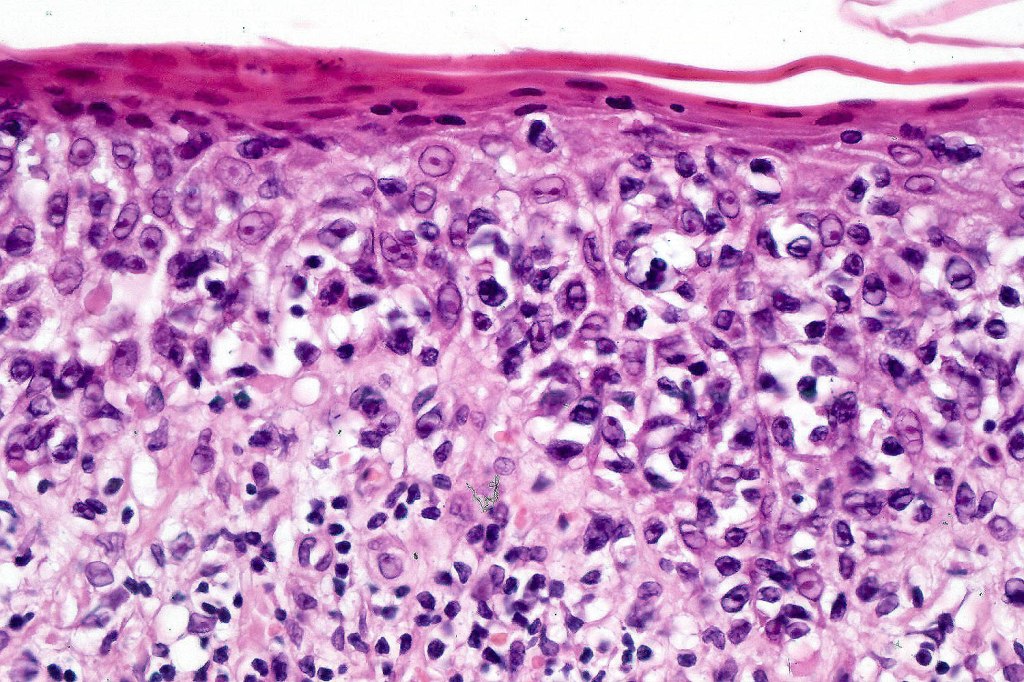

Histological features

The histological hallmark of mycosis fungoides is the presence of large atypical lymphocytes with a convoluted/cerebriform nuclear border (Sézary cells). These may be found at the epidermal-dermal jnuction and as collections within the epidermis (Pautrier microabscess). These are most easily found in plaque stage disease. The epidermal component can be subtle in patch stage disease and is often lost in tumor stage dsease. The classification into patch, plaque & tumor stage disease is less helpful histologically as the features merge from one to the other. It is all a matter of degree.

Tumor Stage Disease

•Epidermotropism is often minimal or absent

•Dense, broad diffuse or nodular, dermal infiltrate often extending into the subcutaneous fat

•Abundant Sézary cells. Frequently accompanied by very pleomorphic forms

•Mitoses often abundant, frequently abnormal

•CD30 expression correlates with transformation (cells X4 size of small lymphocytes comprising 25% or more of the infiltrate or the presence of a distinct large nodule)